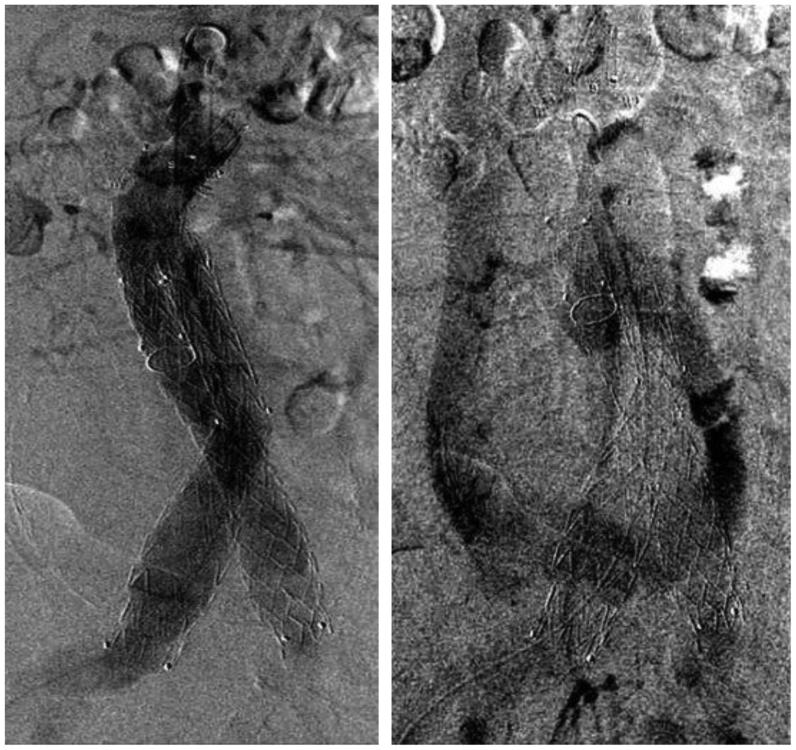

A primary aortocaval fistula (ACF) is a rare complication of abdominal aortic aneurysms caused by erosion of the aortic wall into the vena cava. It is more frequently observed in the setting of ruptured abdominal aortic aneurysms and presents a unique challenge for vascular surgeons. Both open and endovascular techniques exist, with the main differences being perioperative mortality and recurrence rates. We present a case of an ACF diagnosed intraoperatively, which persisted after endovascular aneurysm repair in conjunction with a type II endoleak. We applied a unique staged, triple endovascular approach to close the ACF via caval and aortic exclusion of inflow and outflow vessels.

原发性主动脉腔静脉瘘(ACF)是腹主动脉瘤的一种罕见并发症,由主动脉壁侵蚀进入腔静脉所致。在破裂性腹主动脉瘤中更常观察到,对血管外科医生构成独特挑战。开放手术和血管内技术都存在,主要区别在于围手术期死亡率和复发率。我们报告一例术中诊断为ACF的病例,该病例在血管内动脉瘤修复术后伴有II型内漏持续存在。我们采用了一种独特的分期、三重血管内方法,通过腔静脉和主动脉对流入和流出血管的封堵来闭合ACF。